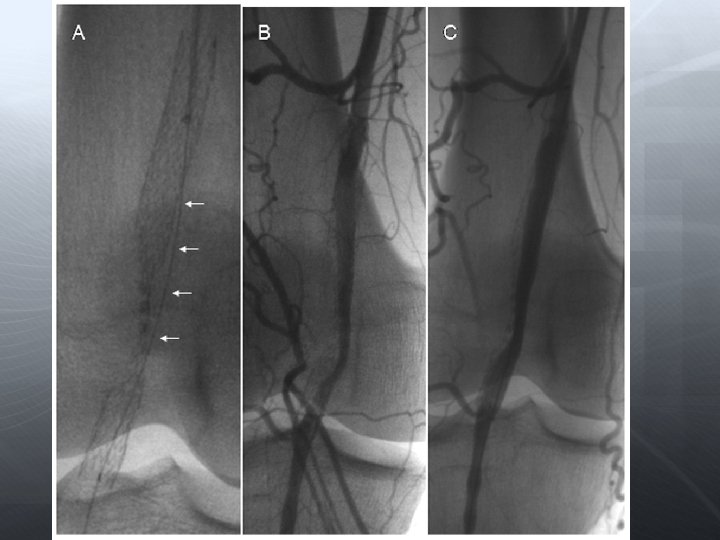

SFA

Re-entry cihazı

DİZALTI